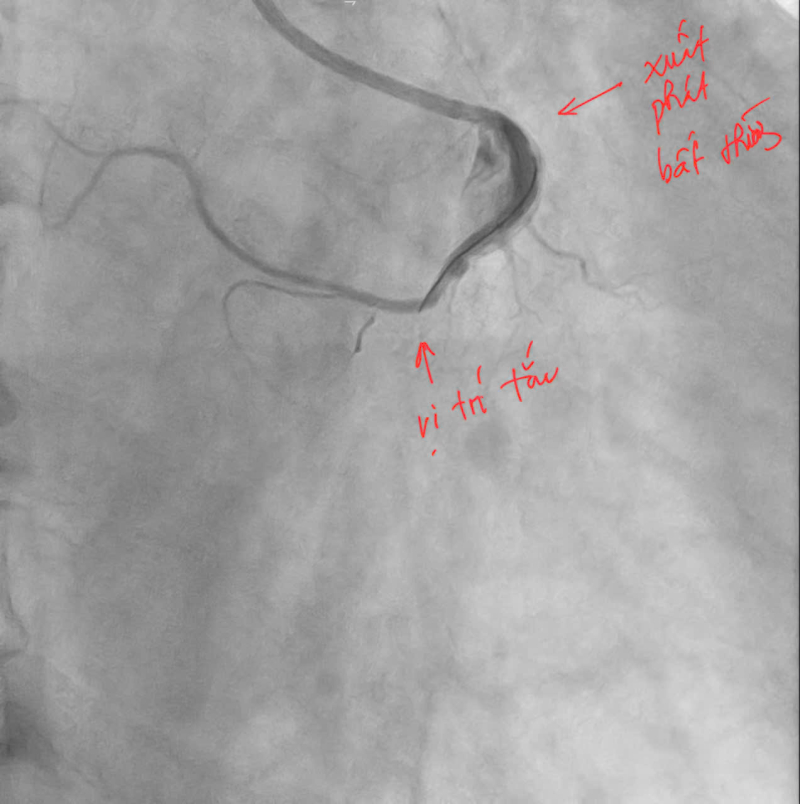

Ngay lập tức, bệnh nhân được kích hoạt quy trình cấp cứu tim mạch và chuyển tới phòng can thiệp mạch vành khẩn cấp. Kết quả chụp mạch vành cho thấy bệnh nhân bị tắc hoàn toàn động mạch vành phải đoạn 2 (RCA 2). Đáng chú ý, động mạch vành phải của bệnh nhân có vị trí xuất phát bất thường từ xoang vành trái của động mạch chủ – một dạng dị dạng hiếm gặp khiến việc tiếp cận và can thiệp trở nên phức tạp hơn nhiều so với các trường hợp thông thường.

Tuy nhiên, ngay sau khi đặt stent, bệnh nhân xuất hiện tình trạng No-Reflow – tức là lòng mạch đã được mở nhưng dòng máu vẫn không lưu thông hiệu quả do co thắt vi mạch hoặc tổn thương vi tuần hoàn. Đây là một biến chứng nguy hiểm trong can thiệp mạch vành, có thể khiến cơ tim tiếp tục bị thiếu máu và làm tăng nguy cơ tử vong nếu không xử trí kịp thời.

Ê-kíp can thiệp đã nhanh chóng triển khai nhiều biện pháp xử trí, trong đó có tiêm trực tiếp thuốc giãn mạch vào lòng động mạch vành như Adenosine nhằm giảm co thắt và cải thiện vi tuần hoàn. Sau khi xử trí tích cực, dòng chảy mạch vành đã được khôi phục với mức dòng chảy TIMI 2, giúp ổn định tình trạng cho người bệnh.

Hình ảnh: Sau can thiệp